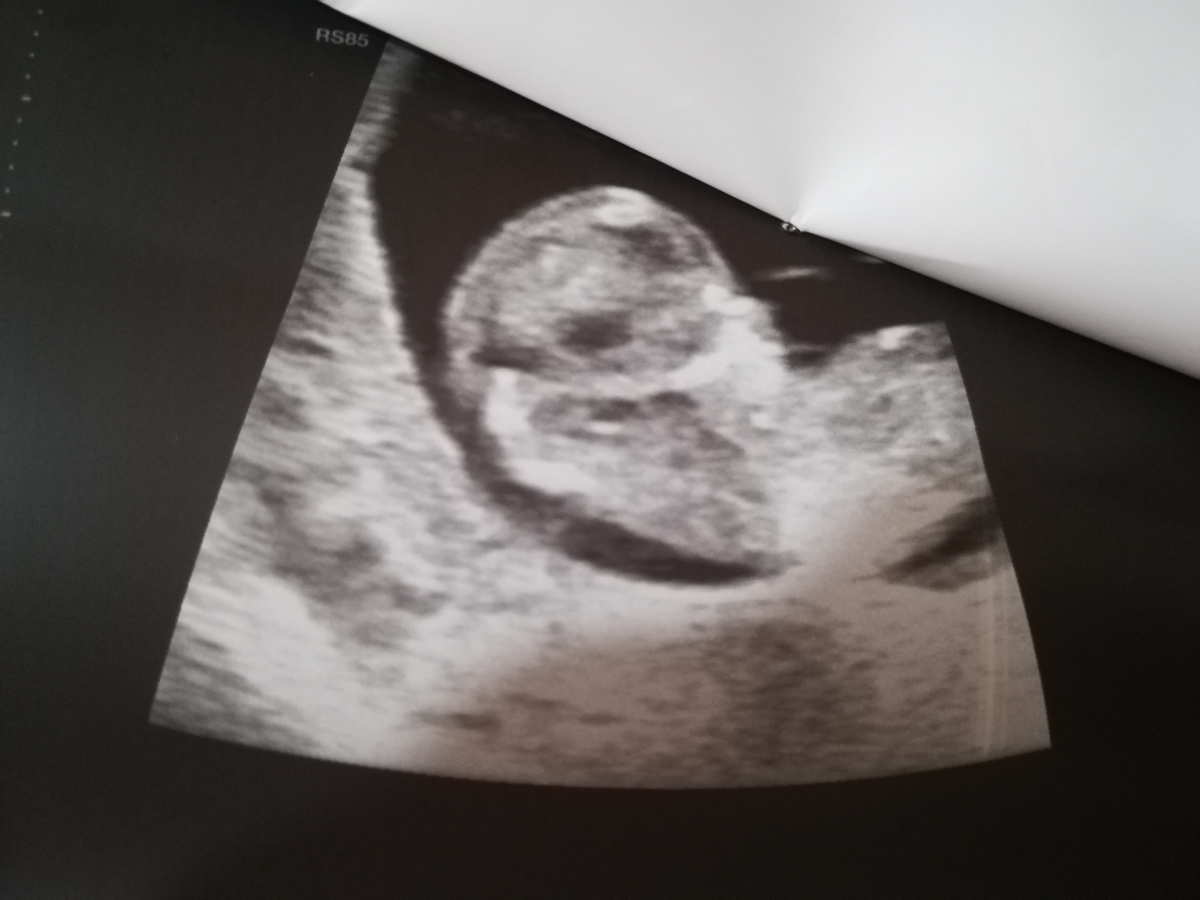

سونو NT انجام دادم میشه برا منم حدس بزنید نی نی چیه؟ دکترم احتمال داد بعدش میگم

از روی این عکس احتمال زیاد دختره چون سرش گرده

ولی تو بقیه عکس ها پسر چون سرش حالت مربعی شکل داره

من از یه دکتری پرسیدم گفت جنین دختر سرش گرده و پیشونی هم همینطور

ولی جنین پسر سرش مربعی شکله